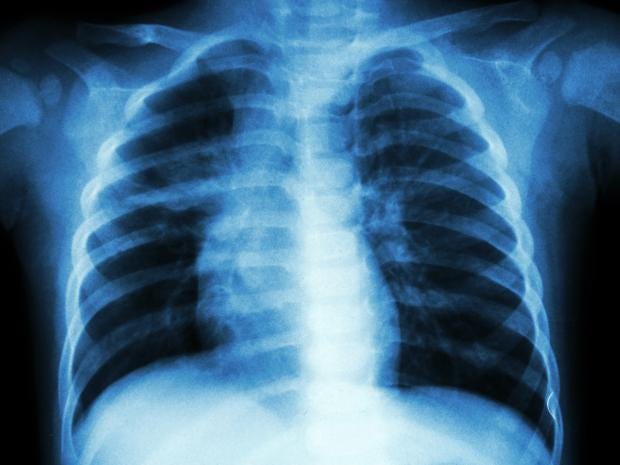

Researchers “misrepresented” the results of animal studies in order to obtain funding and approval for human trials for a new tuberculosis vaccine, a study claims.

The investigation by the British Medical Journal examined MVA85A, a vaccine developed by a team at Oxford University which supposedly boosted the efficacy of the BCG vaccine to provide greater protection against Tuberculosis.

The drug was reported to have been effective in animal studies, but subsequently failed to show a benefit when tested in a large clinical trial in South African infants in 2009.